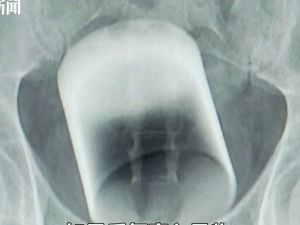

NASIL OLDU BU İŞ! ANÜSÜNDE BARDAK ÇIKTI...